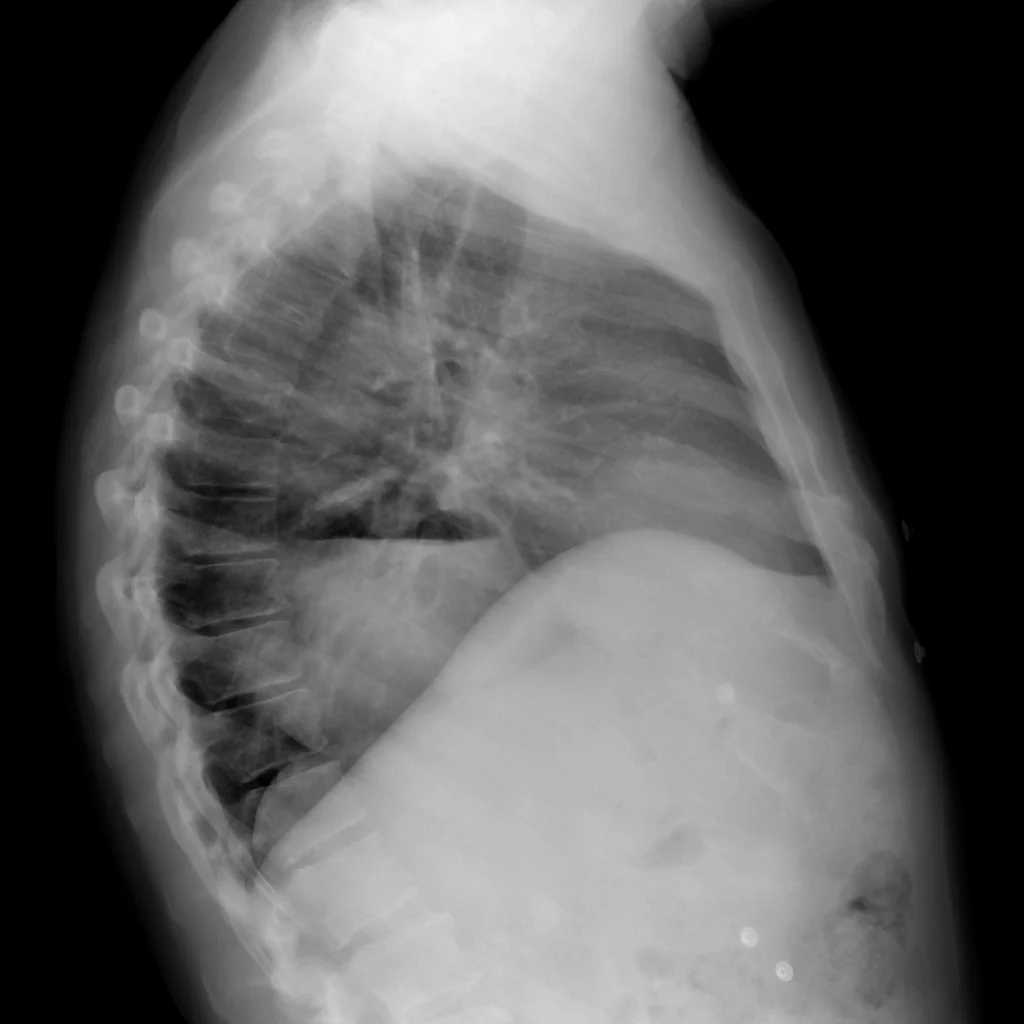

Radiología

Rx de tórax LL. La proyección lateral confirma la posición posterior de la imagen, y demuestra una pared propia (la del estómago) confirmado el contenido mixto con nivel hidroaéreo.